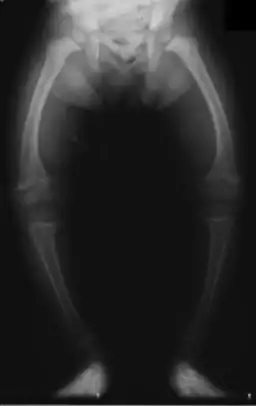

Primidone, along with phenytoin and phenobarbital, is one of the anticonvulsants most heavily associated with bone diseases such as osteoporosis, osteopenia (which can precede osteoporosis), osteomalacia and fractures.[31][32][33] The populations usually said to be most at risk are institutionalized people, postmenopausal women, older men, people taking more than one anticonvulsant, and children, who are also at risk of rickets.[31] However, it has been suggested that bone demineralization is most pronounced in young people (25–44 years of age)[32] and one 1987 study of institutionalized people found that the rate of osteomalacia in the ones taking anticonvulsants—one out of nineteen individuals taking an anticonvulsant (vs. none among the thirty-seven people taking none) —was similar to that expected in elderly people. The authors speculated that this was due to improvements in diet, sun exposure and exercise in response to earlier findings, and/or that this was because it was sunnier in London than in the Northern European countries which had earlier reported this effect.[33] In any case, the use of more than one anticonvulsant has been associated with an increased prevalence of bone disease in institutionalized epilepsy patients versus institutionalized people who did not have epilepsy. Likewise, postmenopausal women taking anticonvulsants have a greater risk of fracture than their drug-naive counterparts.[31]

Anticonvulsants affect the bones in many ways. They cause hypophosphatemia, hypocalcemia, low Vitamin D levels, and increased parathyroid hormone. Anticonvulsants also contribute to the increased rate of fractures by causing somnolence, ataxia, and tremor which would cause gait disturbance, further increasing the risk of fractures on top of the increase due to seizures and the restrictions on activity placed on epileptic people.Increased fracture rate has also been reported for carbamazepine, valproate and clonazepam. The risk of fractures is higher for people taking enzyme-inducing anticonvulsants than for people taking non-enzyme-inducing anticonvulsants.[32] In addition to all of the above, primidone can cause arthralgia.[24]